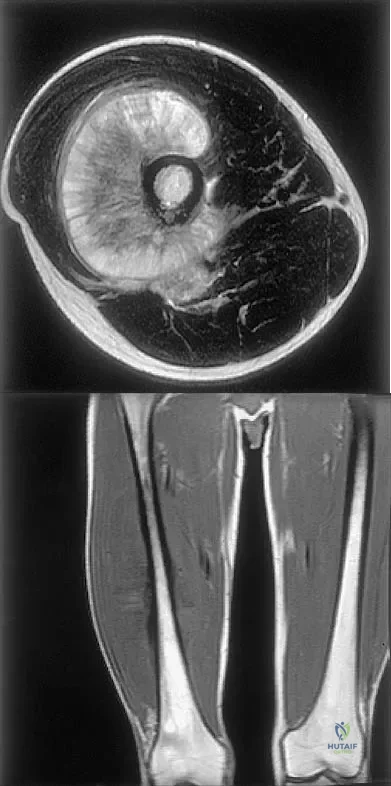

Figures 35a and 35b show the axial T2-weighted and coronal T1-weighted MRI scans of a patient who has enlargement of the right thigh. What is the most likely diagnosis?

A 14-year-old boy reports pain in the distal thigh. He denies any history of trauma. Examination reveals tenderness and swelling of the distal thigh without effusion. A radiograph and CT scan are shown in Figures 10a and 10b. A biopsy specimen is shown in Figure 10c. Management should consist of